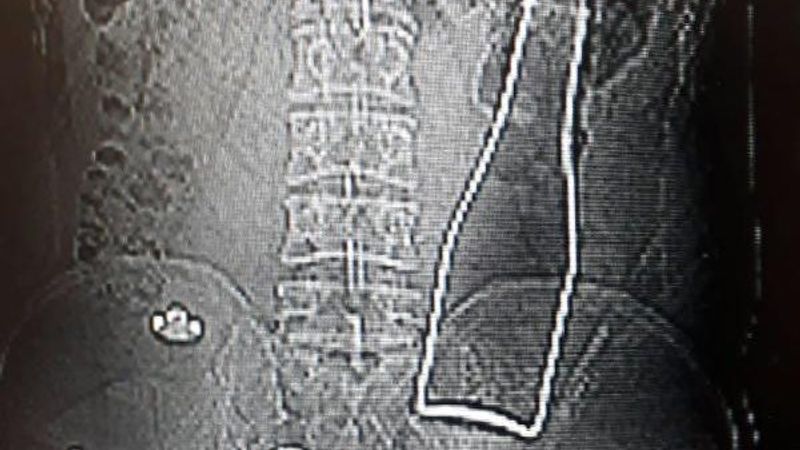

Karaman'da karın ağrısı şikayetiyle hastaneye giden Afganistan uyruklu A.E. adlı erkeğin, çekilen röntgen filminde beklenmedik bir durumla karşılaşıldı.

Röntgene yansıyanlara göre, A.E.'nin kalın bağırsağında şişe olduğu ortaya çıktı.

27 yaşındaki A.E.'nin makatından sokulduğu belirtilen soda şişesi, yaklaşık 1 saat süren ameliyatla alındı. A.E.'nin olayla ilgili verdiği ifade belli oldu.